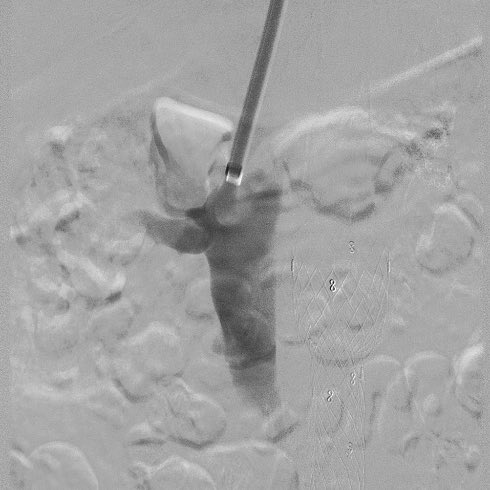

This #IVCfilter was placed after a #trauma in a patient with DVT. During removal, the apex was imbedded and removed with standard equipment using the “hangman” aka “loop sling” technique of flossing a glide wire through the apex #iRad